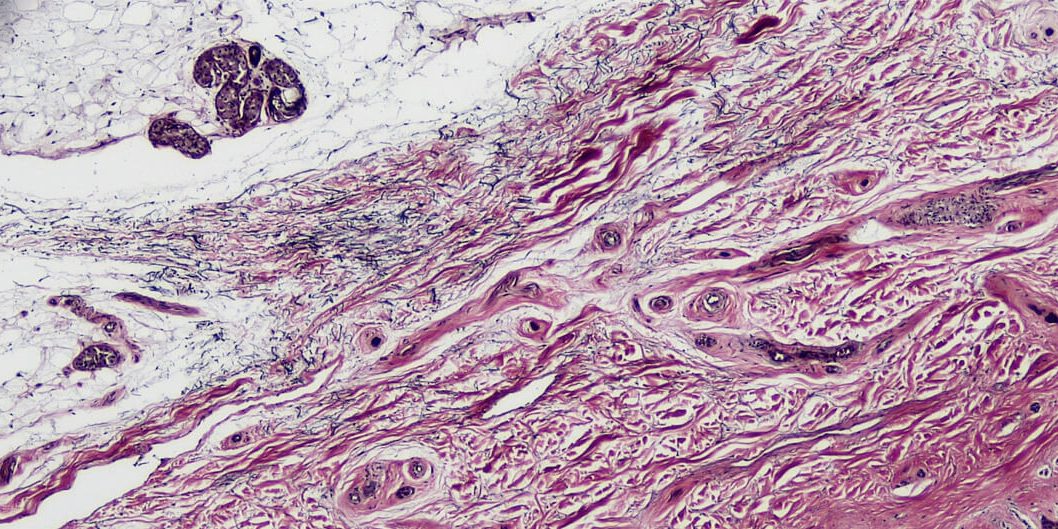

Ο συνδετικός ιστός γνωρίζουµε πως επιτελεί διάφορες λειτουργίες καθώς σε αυτόν ανήκουν οι ιστοί χονδρικός και οστίτης, το αίµα και ο στηρικτικός ιστός. Ο συνδετικός ιστός αποτελείται από κύτταρα, ίνες και εξωκυττάρια θεµέλια ουσία. Στο άρθρο αυτό θα µας απασχολήσει ο στηρικτικός ιστός, κύρια χαρακτηριστικά του οποίου είναι οι εξωκυττάριες ίνες και η θεµέλια ουσία. Ο συνδετικός ιστός οµαδοποιείται κατά τύπους: α) ο εµβρυϊκός συνδετικός ιστός ή µεσέγχυµα από τον οποίο προέρχονται σχεδόν όλα τα είδη των κυττάρων του συνδετικού ιστού β) ο πυκνός συνδετικός ιστός ο οποίος είναι δοµικό υλικό των τενόντων και των συνδέσµων, ενώ επίσης στηρίζει την επιδερµίδα και σχηµατίζει την προστατευτική κάψα που περιβάλλει το ήπαρ και το σπλήνα, γ) ο χαλαρός συνδετικός ιστός που γεµίζει τους ενδιάµεσους χώρους και υποστηρίζει τα όργανα, δ) ο λιπώδης συνδετικός ιστός ο οποίος αποθηκεύει λίπος και ε) ο δικτυωτός συνδετικός ιστός ο οποίος έχει υποστηρικτικό ρόλο σε διάφορα όργανα1, 2, 3.

Οι περιτονίες είναι ένα ιδιαίτερο δίκτυο συνδετικού ιστού που βρίσκεται σε ολόκληρο το σώµα για την προστασία και στήριξη δοµών του σώµατος. Για εκπαιδευτικούς λόγους µπορεί να χωριστεί στην επιπολής περιτονία, την εν τω βάθει περιτονία και την βαθύτερη περιτονία. Η επιπολής περιτονία αλλιώς λέγεται υποδόριος ιστός, είναι χαλαρός συνδετικός ιστός που εντοπίζεται κάτω από το χόριο του δέρµατος. Η περιτονία αυτή περιέχει εναποθέσεις λίπους οι οποίες αν αυξηθούν δηµιουργούν κυρίως την πρωτογενή κυτταρίτιδα. Η εν τω βάθει περιτονία είναι ινώδης συνδετικός ιστός που βρίσκεται κάτω από την επιπολής περιτονία. Η περιτονία αυτή περιβάλλει µύες και µυϊκές οµάδες και εµπεριέχει το επιµύϊο που περιβάλλει τον καθένα µυ ξεχωριστά, το περιµύϊο που περιβάλλει τα µυϊκά δεµάτια του κάθε µυ και το ενδοµύϊο που περιβάλει την κάθε µυϊκή ίνα. Εκτός από τους µύες η εν τω βάθει περιτονία περιβάλει αδένες νεύρα και αγγεία, ενώ σε πολλά σηµεία του σώµατος συνδέεται µε το περιόστεο. Η βαθύτερη περιτονία βρίσκεται µέσα στην σκληρά µήνιγγα και προστατεύει το κεντρικό νευρικό σύστηµα4 .